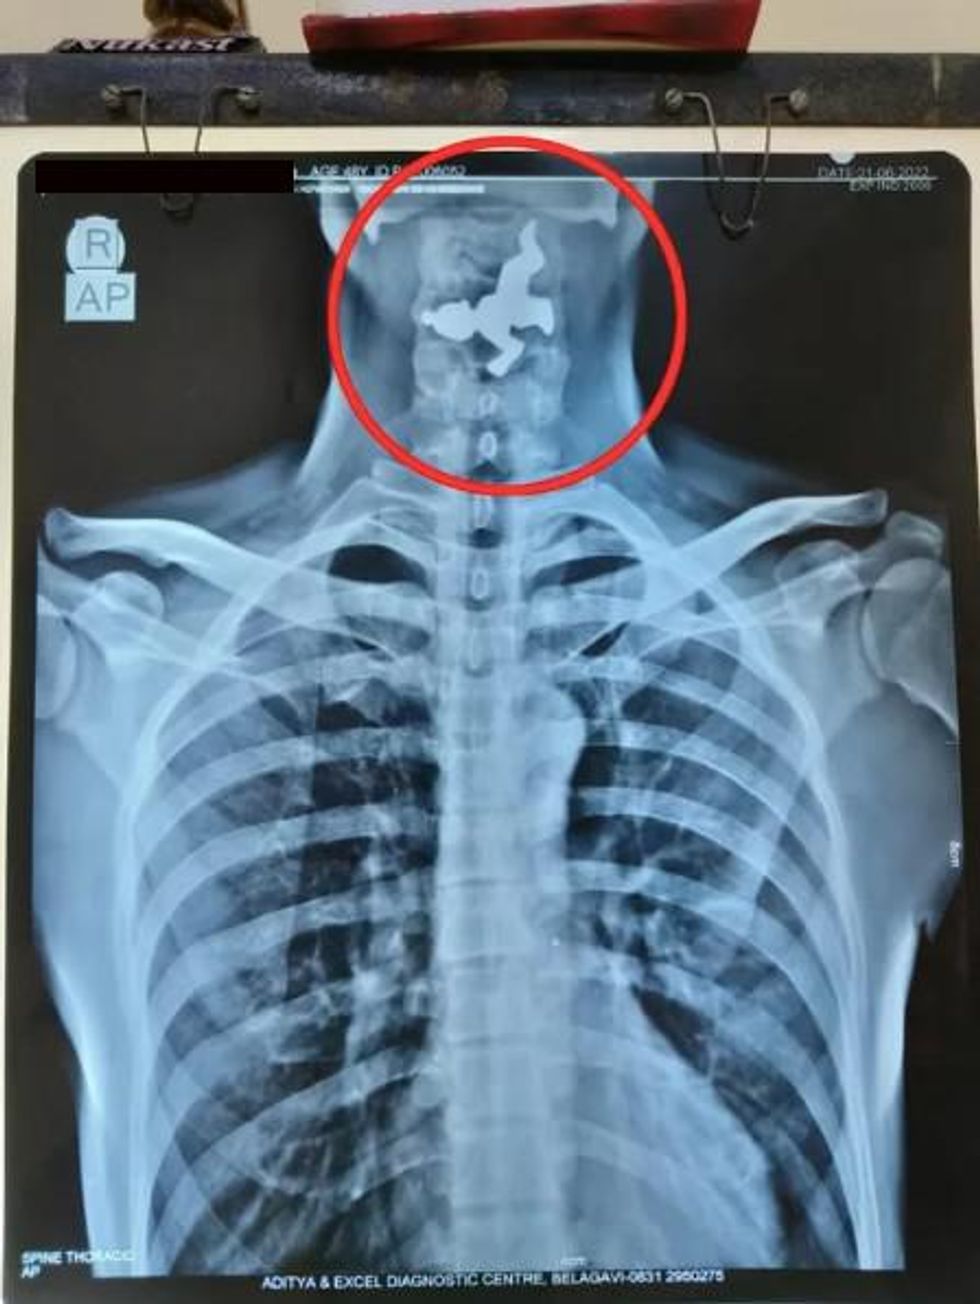

An X-ray was carried out after the patient went to his local surgery complaining of throat problems.

And, incredibly, the scan revealed the outline of a small figure - which was later found to be a model of the deity Krishna.

Pictures of the X-ray show the 5cm figure clearly lodged in the man's throat.